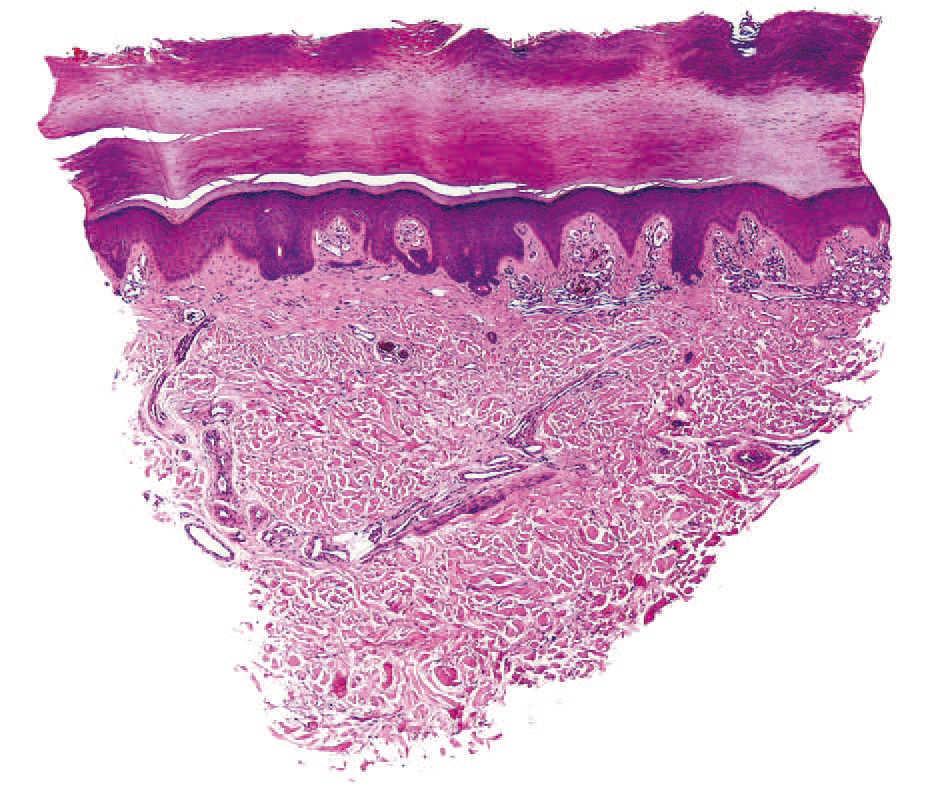

Realizamos una biopsia de la lesión y en el estudio histopatológico destacaba, bajo una epidermis conservada, una proliferación de vasos capilares agrupados en ovillos, con estroma laxo, localizados en las papilas dérmicas (figs. 2 y 3). En el resto de la dermis no existía infiltrado linfocitario ni ningún otro hallazgo patológico. La inmunotinción con CD 31 resultó positiva para las células endoteliales (figs. 4 y 5).

Figura 2. Vasos capilares agrupados en ovillos localizados en las papilas dérmicas. Hematoxilina-eosina, 10.